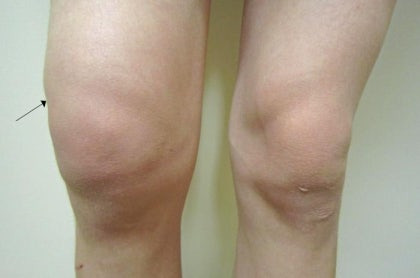

- 좌우 무릎 크기 차이

물이 더 차면 겉으로도 변화가 분명해집니다.

중기 증상의 특징

- 무릎이 눈에 띄게 부음